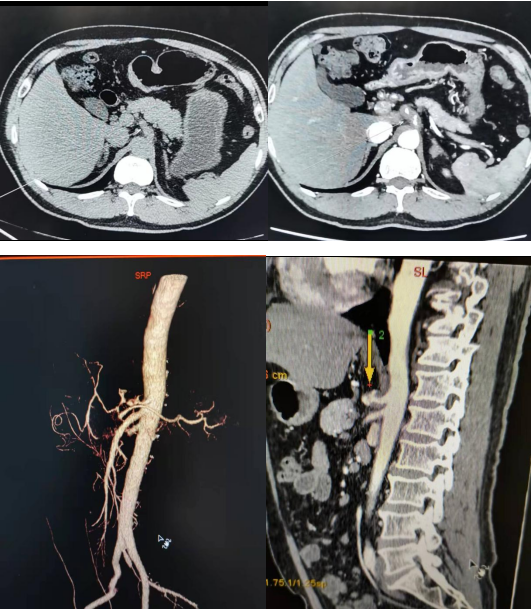

CTA顯示腸系膜上動(dòng)脈可見真假腔,真腔內(nèi)見造影劑,假腔未見造影劑顯影。

平掃腸系膜上動(dòng)脈明顯增粗,邊緣毛糙,周圍脂肪間隙模糊。CTA顯示真假腔,假強(qiáng)較真腔大,并可見潰瘍破口,范圍較長。

平掃腸系膜上動(dòng)脈略增粗,邊緣毛糙;CTA顯示腸系膜上動(dòng)脈內(nèi)膜片移位,形成真假腔,真假腔均顯影。

上腹部CT平掃:1、腹腔干近段形態(tài)略增粗,請結(jié)合臨床,必要時(shí)行CTA進(jìn)一步檢查除外夾層可能。2、雙腎結(jié)石。3、左側(cè)腎上腺內(nèi)側(cè)支結(jié)節(jié)灶,請結(jié)合臨床及復(fù)查。CTA:1、兩肺多發(fā)結(jié)節(jié)灶,建議年度復(fù)查。2、腹腔干、胃左動(dòng)脈及脾動(dòng)脈近段異常,考慮腹腔千夾層(III型)或壁間血腫伴潰瘍。3、左側(cè)腎上腺考慮增生.

平掃腹腔干增粗,邊緣毛糙;CTA示腹腔干真腔顯影,并見多個(gè)潰瘍破口,假腔未見顯影。

擬診為ISMAD或ICAD時(shí),上腹部CT平掃能提供線索:腸系膜上動(dòng)脈形態(tài)不規(guī)則,局部增粗,周圍間隙模糊,脂肪密度增高;確診首選檢查方法是腹主動(dòng)脈CTA,重點(diǎn)觀察包括腸系膜上動(dòng)脈在內(nèi)的腹腔臟器動(dòng)脈血管,利用VR、MPR、CPR等多項(xiàng)后處理技術(shù),逐一分析。影像確診為ISMAD或ICAD時(shí),應(yīng)進(jìn)一步分型,其分型結(jié)果,對臨床治療有極重要指導(dǎo)意義。